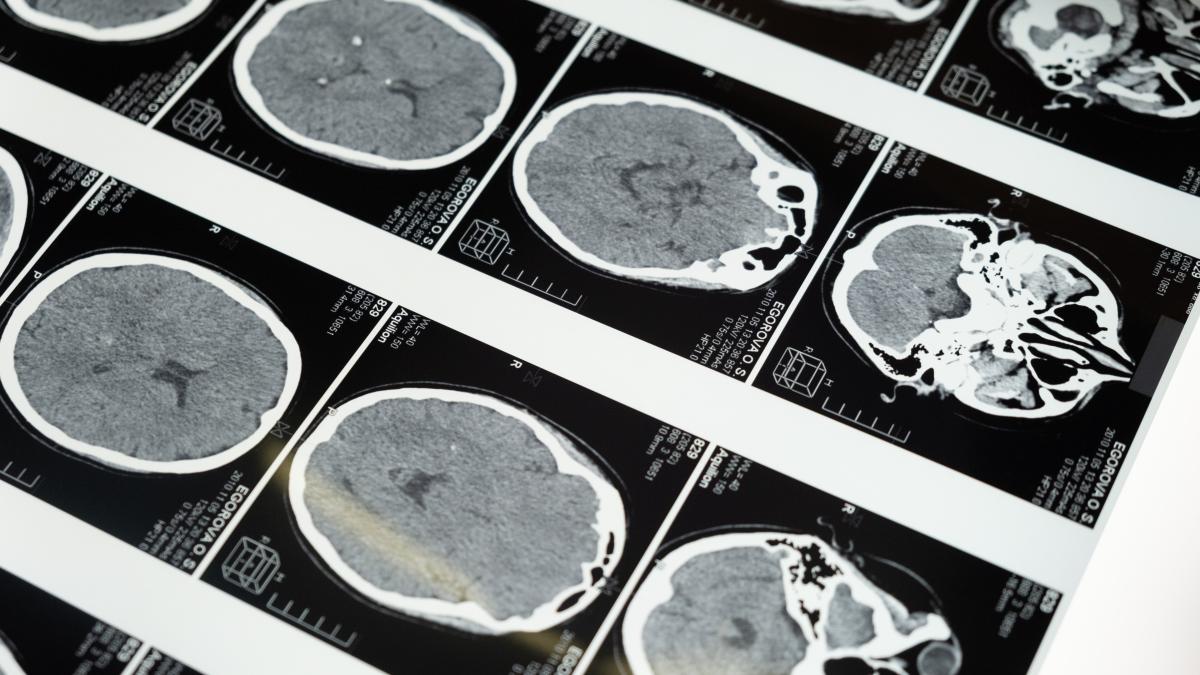

care-este-diferenta-dintre-rmn-si-ct_37080700 Imagine cu rol ilustrativ / Sursa foto: Pexels

O scanare CT este o formă de radiografie care implică un aparat mare de raze X. Este utilizată pentru fracturi osoase, tumori, monitorizarea cancerului sau pentru a constata dacă există sângerări interne. Pacientul trebuie să stea întins pe o masă. Un aparat se deplasează și prin scanarea CT se fac fotografii în secțiune transversală în interiorul corpului.

Scanarea CT este mai rapidă și poate oferi imagini ale țesuturilor, organelor și structurii scheletice.  RMN-ul este foarte abil în capturarea imaginilor care îi ajută pe medici să stabilească dacă există țesuturi anormale în corp. Sunt mai detaliate în imaginile lor.